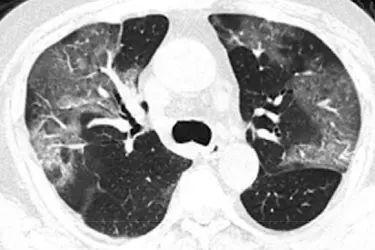

HRCT Chest is the best diagnostic test for Covid-19 and is more sensitive than RT PCR test. Very thin slices are taken which gives much higher resolution images in High Resolution Lung CT. The test is non-invasive and can be completed in less than a minute. Hundreds of images are produced which are then studied by the radiologists to prepare the report. Any kind of tumour or lesion in the lungs can be best seen on CECT Chest which is Contrast Enhanced Lung CT. In this test non-ionic contrast is inected through an injection or pressure injector to complete the study. Patients suffering from Chronic Lung Disease, Respiratory problems, shortness of breath, smokers etc should get this test done on the advice of their doctor to know the status of lungs. All the patients who have been found Covid positive on RT PCR test and had symptoms should also get HRCT Chest done to gauge the damage to the lungs due to Covid infection. Another good test to see the health of the lungs is Bronchoscopy but it is an invasive test and requires short hospitalization. CT Scan on the other hand is completely non-invasive and requires no hospitalization.

NCCT Chest or HRCT Chest does not require any preparation and can be done at any time of the day. For CECT Chest you have to report at our centre on empty stomach with overnight fasting. Normally the appointment is given for 9am. On arrival of the patient at the centre, we would first do a blood test to see the kidney functioning. If the kidney function test is normal then contrast can be given to the patient. For patients with abnormal kidney function, non-contrast MRI is preferred over non-contrast CT Scan. Do not wear any jewellery when you come for the testing. You would be given a hospital gown to wear before the test. The patient has to lie down on the CT Table and the technician would place a canula on the arm or back of the hand. During the examination, contrast is injected through a pressure injector which is connected to the canula. The patient can go home within minutes of the completion of the test. Radiologists would need 6-8 hours for studying the images procured during the test to prepare the report. The films or the CD can be taken immediately after the test while the report is emailed to you within 24 hours.